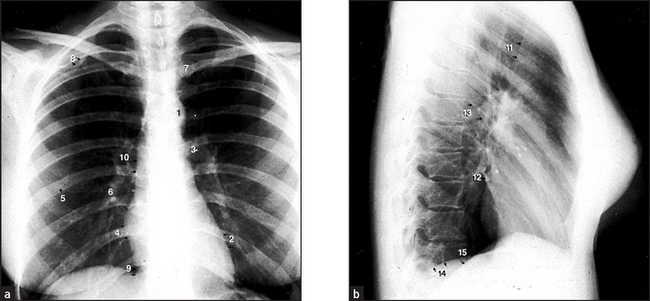

Figure 8.2 Normal chest X-ray (a) The posteroanterior view shows: (1) aortic knuckle; (2) left heart border formed by the lateral border of the left ventricle; (3) left hilum, formed mostly by the left main pulmonary artery and partly by the left upper pulmonary veins; (4) right heart border formed by the right atrium; (5) inferior angle of the scapula; (6) right basal pulmonary artery; (7) medial aspect of the left clavicle; (8) spine of the scapula; (9) right cardiophrenic angle; and (10) superimposition of the right lateral margins of the superior vena cava and the ascending aorta. (b) The lateral view shows: (11) anterior border of the trachea; (12) pulmonary vein, entering the left atrium; (13) oblique fissure; (14) left hemidiaphragm; and (15) right hemidiaphragm.